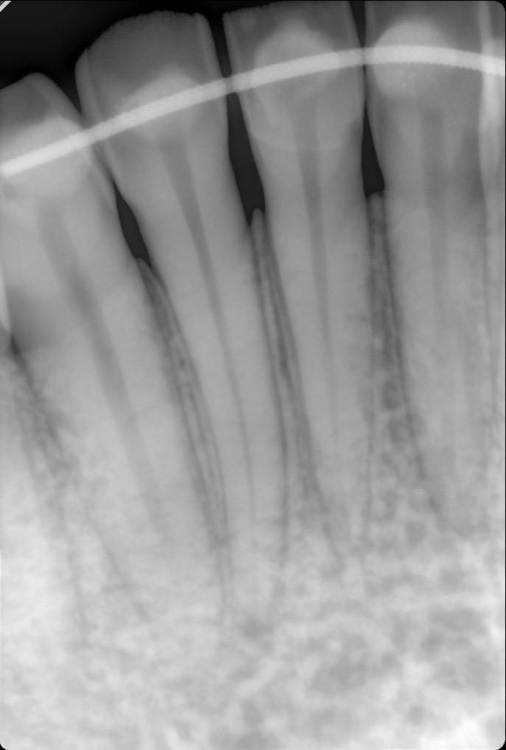

Я сняла брекеты 3,5 года назад. На нижней челюсти был ретейнер, на верхней нет.  Зубы на верхней челюсти сместились, на нижней остались в прежних позициях и зуб двойка снизу справа стал первой точкой контакта челюстей и оказался под большой нагрузкой. Таков был единственый вердикт стоматологов, объясняющий почему эта двойка болит на холодное и горячее. Чтобы избавиться от боли без эндолечения я решила пройти ортодонтическое лечение заново. Выбор пал на Инвизилайн, но несмотря на уже оплаченый план лечения меня терзают сомнения могу ли я с зубом в таком состоянии начинать лечение. Спрашивала можно ли начинать лечить отдельно верх, потом когда уйдет нагрузка с зуба подключить низ. Ортодонт сказала нет, инвизилайн начинают одновременно верх и низ. Вопрос можно ли начинать лечение в таком состоянии двойки? И есть ли альтернативы помочь ситуации без ортодонтии и эндодонтии, мне предлагали подпилить зуб, но я не уверена нормальный ли это выход, не вызовет ли это больших проблем с чувствительностью, не спровоцирует ли отмирание нерва? Состояние 35,36 прошу не комментировать, снимку полгода, с тех пор ситуация с ними изменилась.